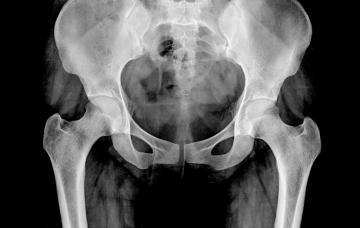

La osteomalacia afecta al metabolismo óseo y reduce la mineralización de los huesos en las personas mayores, causando dolor e incluso fracturas óseas.

Para el diagnóstico de osteomalacia se realizan análisis de laboratorio de sangre y oriena y pruebas de imagen. En último caso de hace una biopsia ósea.